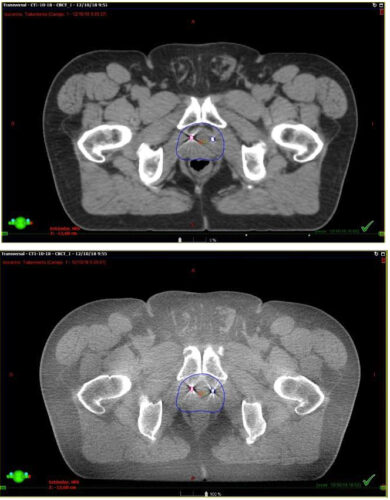

Se presentan figuras de un caso clínico de nuestro centro. Paciente de 57 años, APE: 6.5, Biopsia Gleason 7 (3+4) 2/6 sextantes. Etapificación (-), Rechaza cirugía.